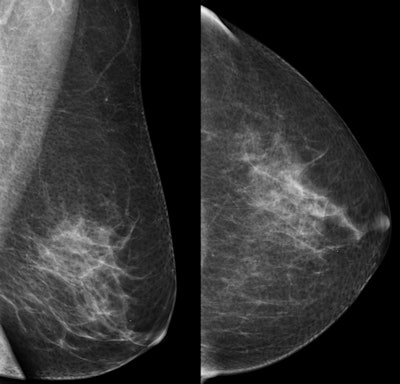

While mammography is the only proven modality to effectively detect cancer, its sensitivity declines with increasing density of breast tissue. So how can radiologists prevent women with dense breasts from slipping through the screening net?

The overall sensitivity rates for mammography only and mammography plus ultrasound for women with dense and nondense breasts are shown in the table below.

Sensitivity rates for dense & nondense breasts | ||

Total 66,680 women | Sensitivity for dense breasts | Sensitivity for nondense breasts |

Mammography alone | 61.5% | 86.6% |

Mammography plus ultrasound | 81.3% | 95.0% |

The absolute gain in sensitivity was 19.8% in women with dense breasts and 8.4% in women with nondense breasts.